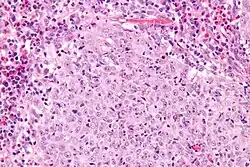

Micrograph of a glassy cell carcinoma of the cervix. H&E stain.

Under the microscope, glassy cell carcinoma tumours are composed of cells with a glass-like cytoplasm, typically associated with an inflammatory infiltrate abundant in eosinophils and very mitotically active. PAS staining highlights the plasma membrane.[2]